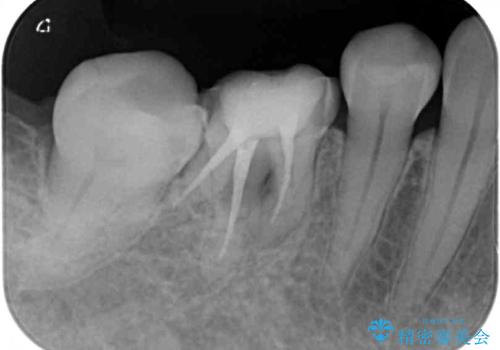

- 奥歯のクラウンが外れたままにしているとのことで来院された患者様です。

奥歯に特に症状はなかったのですが、排膿路が歯肉に認められたため、根管治療を行った上でオールセラミッククラウンにて補綴治療を行うこととしました。